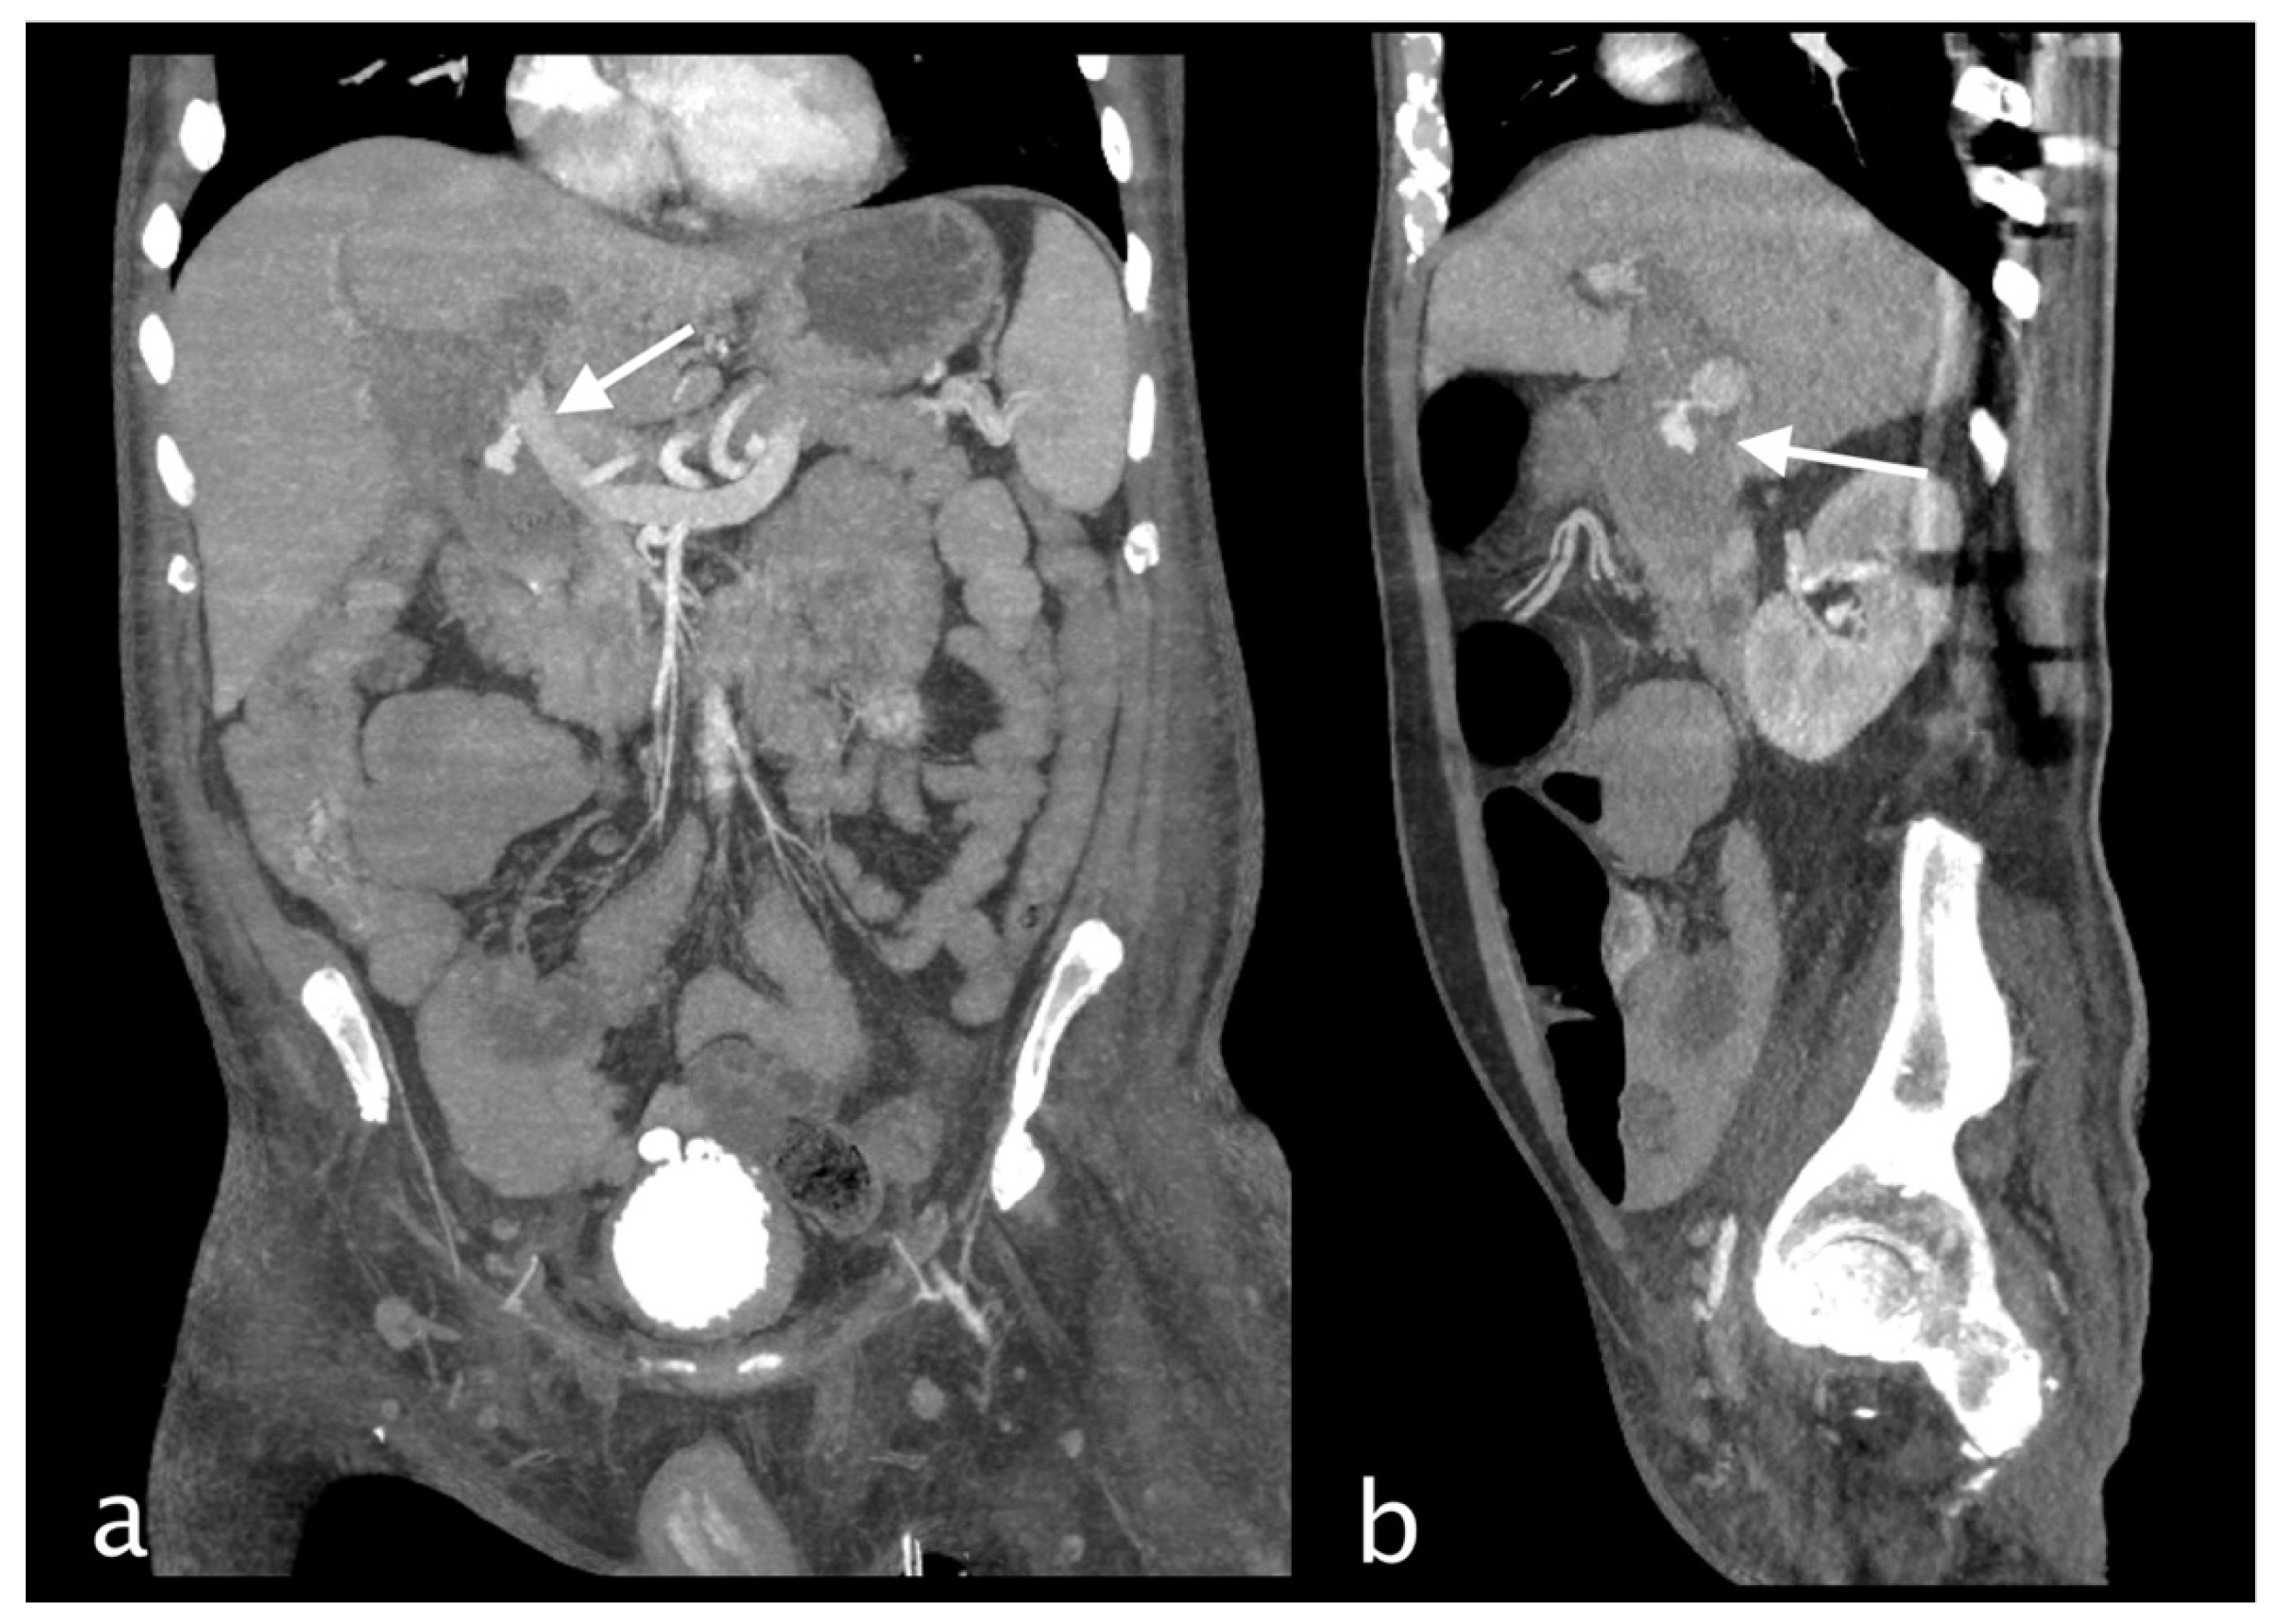

Figure 3.

Hemodynamically stable 30 years old male who underwent MVA trauma (Hb 11,9 g/dl, n.v. 13-18; PCR 0,43 mg/dl, n.v. 0.0-0.5; WBC 15,19 103/mm3 n.v. 4.2-10.5). He underwent CT with IV contrast (a non-contrast, b arterial, c venous, d delayed phase) that showed subcapsular and pericholecystic hematoma, laceration with non-active bleeding of the fourth hepatic segment and cystic artery active bleeding (a,white arrow) along the anterior gallbladder profile with conspicuous increase of contrast extravasation in portal (c)and delayed (d) phases.